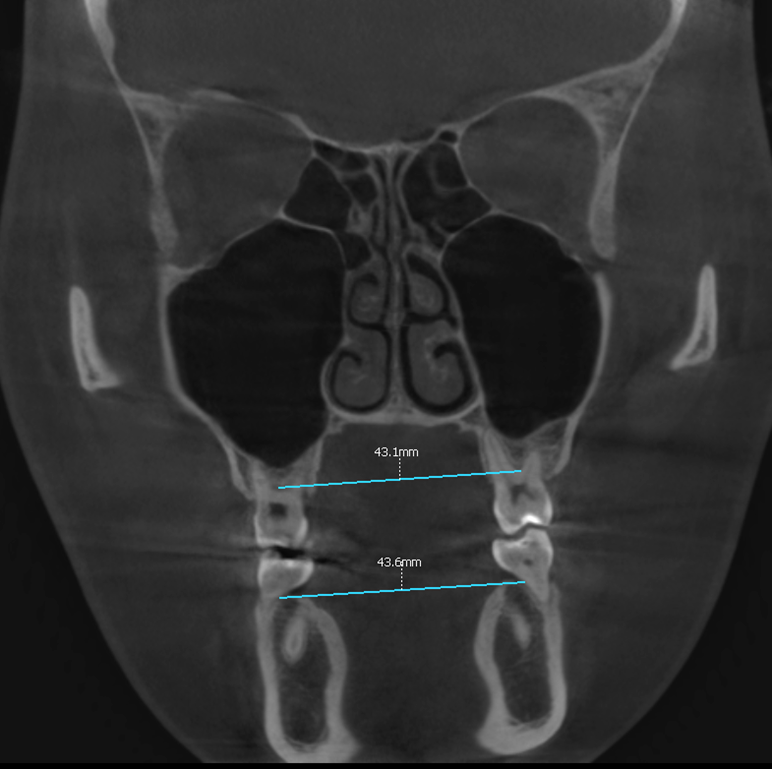

다행히 이번 케이스 에서는 위어금니 간 폭경과

아래 어금니 간 폭경의 비율은 정상이었습니다.

치근 길이가 선천적으로 짧거나 형태가 비정상적인

흡수가 과도하게 일어나는 경우도 있기 때문에,

이동 과정에서도 조금 더 신경을 써야됩니다.

따라서 위와 같은 정밀검사를 통해 유심히 살펴보고

분석해야되는 부분 중 하나입니다.